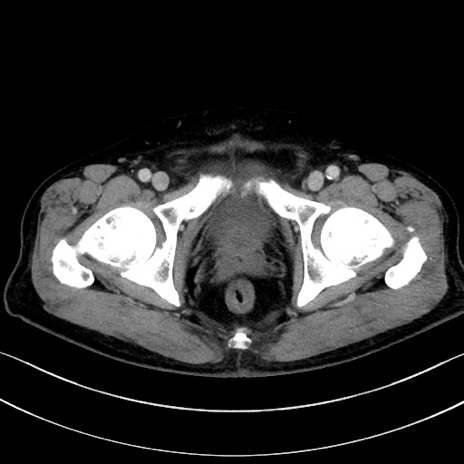

冠状断像

【症例】70歳代男性

【主訴】腹痛

【現病歴】今朝から腹痛あり。全体的に痛い。特に左上の方。排ガスが今日はない。冷や汗が出る。

【既往歴】直腸癌術後

【身体所見】左側腹部〜上腹部に圧痛あり。腹膜刺激症状明らかなではない。軽度反跳痛。左下腹部に術後瘢痕あり。

【データ】WBC 7700、CRP 0.02